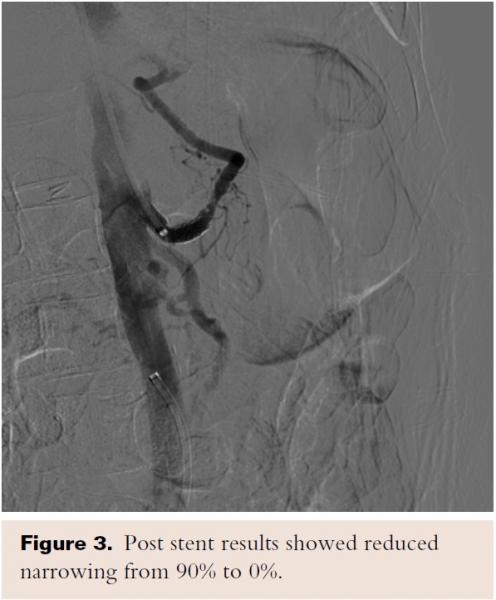

A discussion with the patient regarding treatment options was done, and considering her comorbidities and patient preference, the decision was made for minimally invasive endovascular stenting. A selective angiography of the celiac trunk was performed via the left brachial artery access using a 5 Fr, 125 cm, MP A-2 catheter (Merit Medical Systems, Inc) over the Supracore guidewire (Abbot Vascular). A 90% stenosis in the celiac trunk was identified, and SMA and IMA had no significant stenoses (Figure 5).